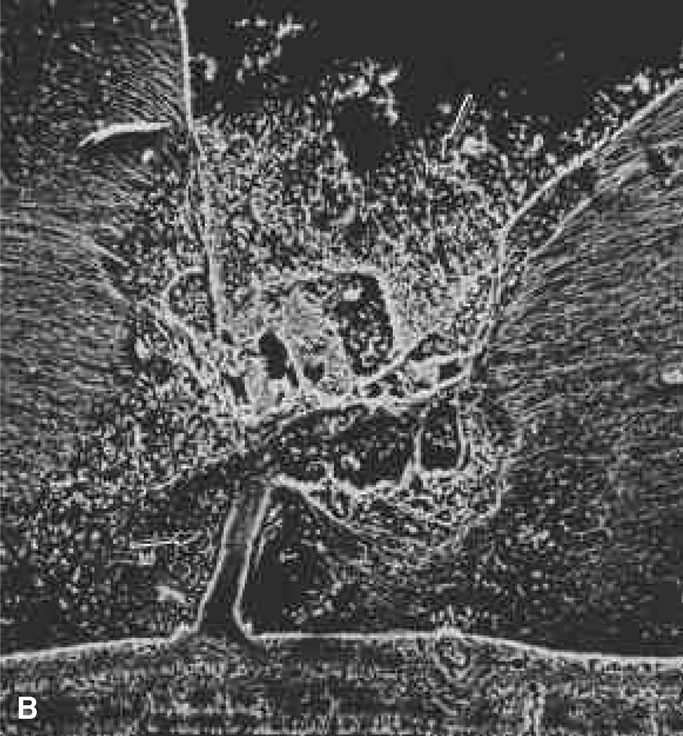

The retina is usually not involved in anterior PHPV. Indeed, previous studies have suggested that the anterior form is due to a primary defect in lens development and that vitreous changes are all secondary.34 This postulate has never been substantiated. There are rare instances of posterior PHPV in which opaque connective tissue arises from Bergmeister's papilla and persistent hyaloid vessels (Fig. 1).32,35 These can cause congenital falciform folds of the retina and, if severe, can cause tentlike retinal folds, leading on rare occasions to tractional and/or rhegmatogenous retinal detachment. Font and investigators36 demonstrated the presence of adipose tissue, smooth muscle, and cartilage within the retrolental plaque and suggested that PHPV arises from metaplasia of mesenchymal elements in the primary vitreous.

Fig. 1. Persistent hyperplastic primary vitreous (PHPV). A wide-angle fundus photograph of the left eye in a 10-year-old boy with the posterior form of PHPV demonstrates a fibrous stalk arising from the optic disc and extending into the central vitreous. (Sebag J: The Vitreous: Structure, Function and Pathobiology, p 99. New York, Springer-Verlag, 1989.)